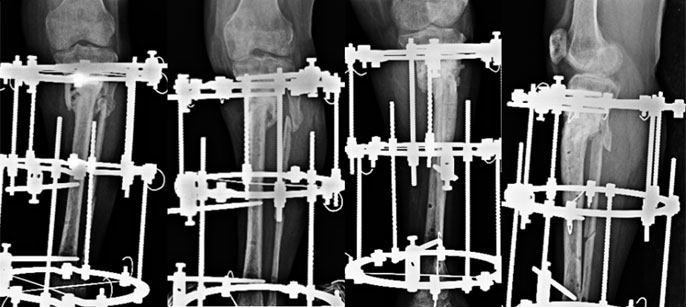

During Treatment

We took up the challenge and an Ilizarov ring fixator was applied. Gradual compression at the fracture site was done and patient allowed to ambulate full weight bearing.

The fracture healed and the fixator was removed but not before 16 months had passed from the surgery. Initially everything went well. Bone grafting was done after 6 months to increase the circumference of healing area. The fracture seemed to be on its way to heal but after about 4 months of bone grafting the proximal wires came loose and had to be reinserted. At the same time the fibula was cut in the middle third to allow collapse at the nonunion site. The fixator was removed after 16 months from the first surgery here. All this while she was walking with the fixator and was largely pain-free apart from occasional discomfort. She is now 8 months post removal and active and freely mobile. (See Testimonial Dr Gayatri Bhat)